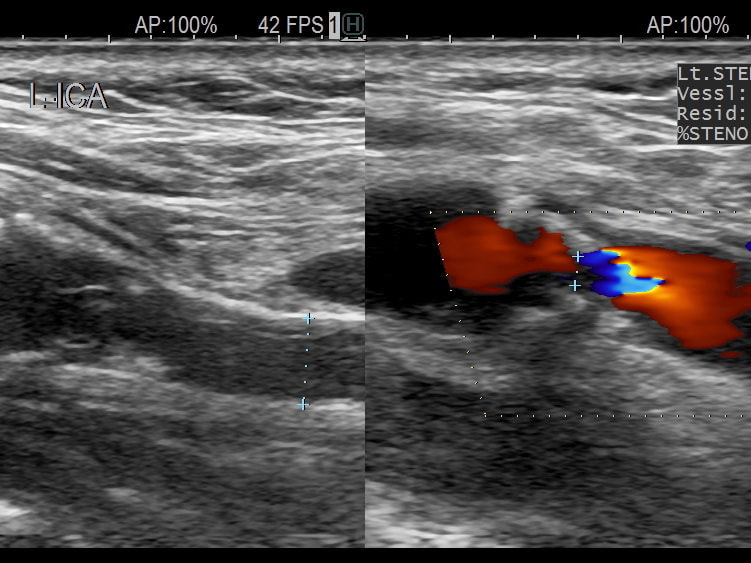

- 頚動脈超音波検査:頚動脈プラークの大きさや性状から、脳梗塞の危険性などがわかります。